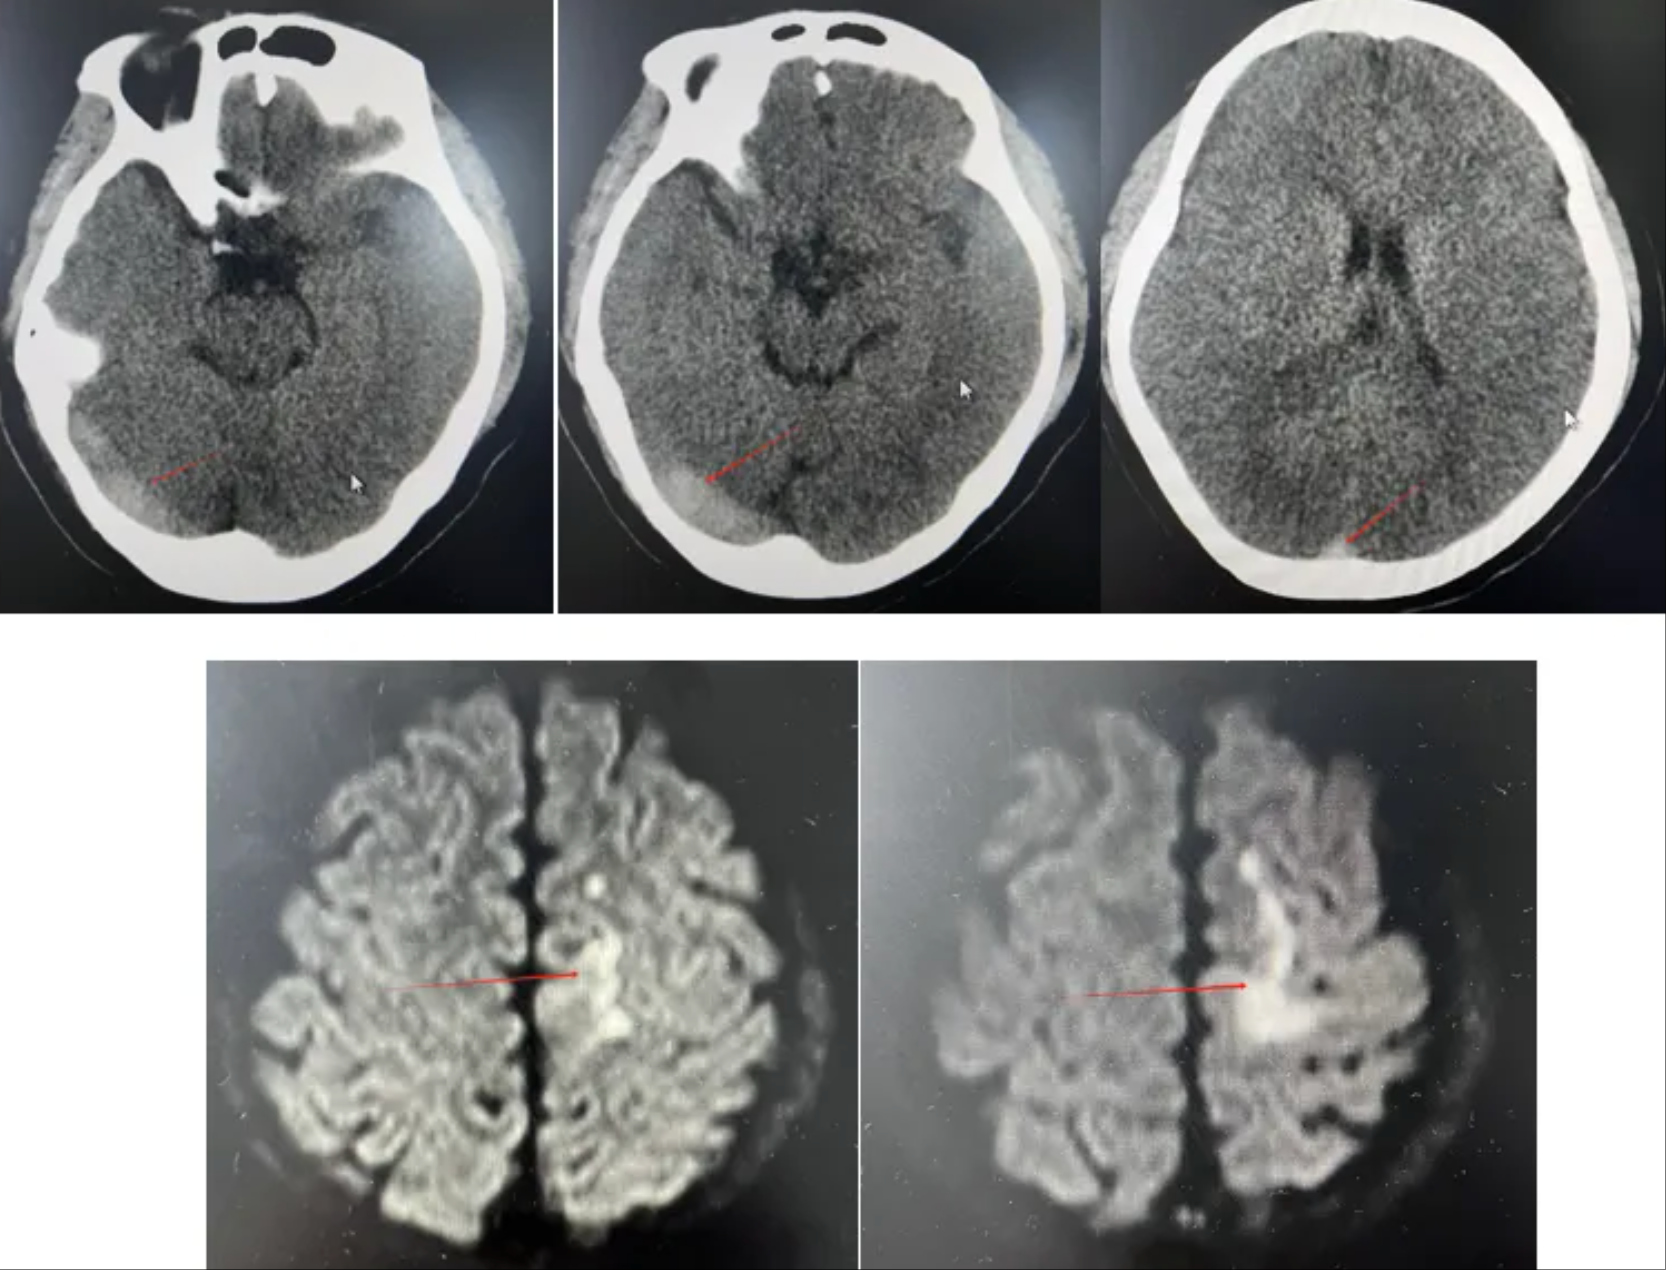

妇科紧急联系针灸科团队马上为她完善相关检查,头颅MRI及头颅MRA提示左侧半卵圆中心新发脑梗死可能,颅内静脉窦血栓待排。经过脑血管造影检查,明确诊断为颅内静脉窦血栓形成。

红线所示:右侧横窦、乙状窦,上矢状窦大负荷血栓形成

针灸诊疗中心主任医师刘桂林介绍,大脑的血管系统就像家里的水管网络,动脉是进水管,把血液输送到大脑,而静脉窦则是关键的“蓄水池”和“出水管”,负责收集用过的血液回流心脏。而刘雯的“蓄水池”和“出水管”被大量血栓完全堵塞了!这直接导致她颅内压飙升到330mm H2O(正常应低于180),如果不及时处理,随时可能脑出血。